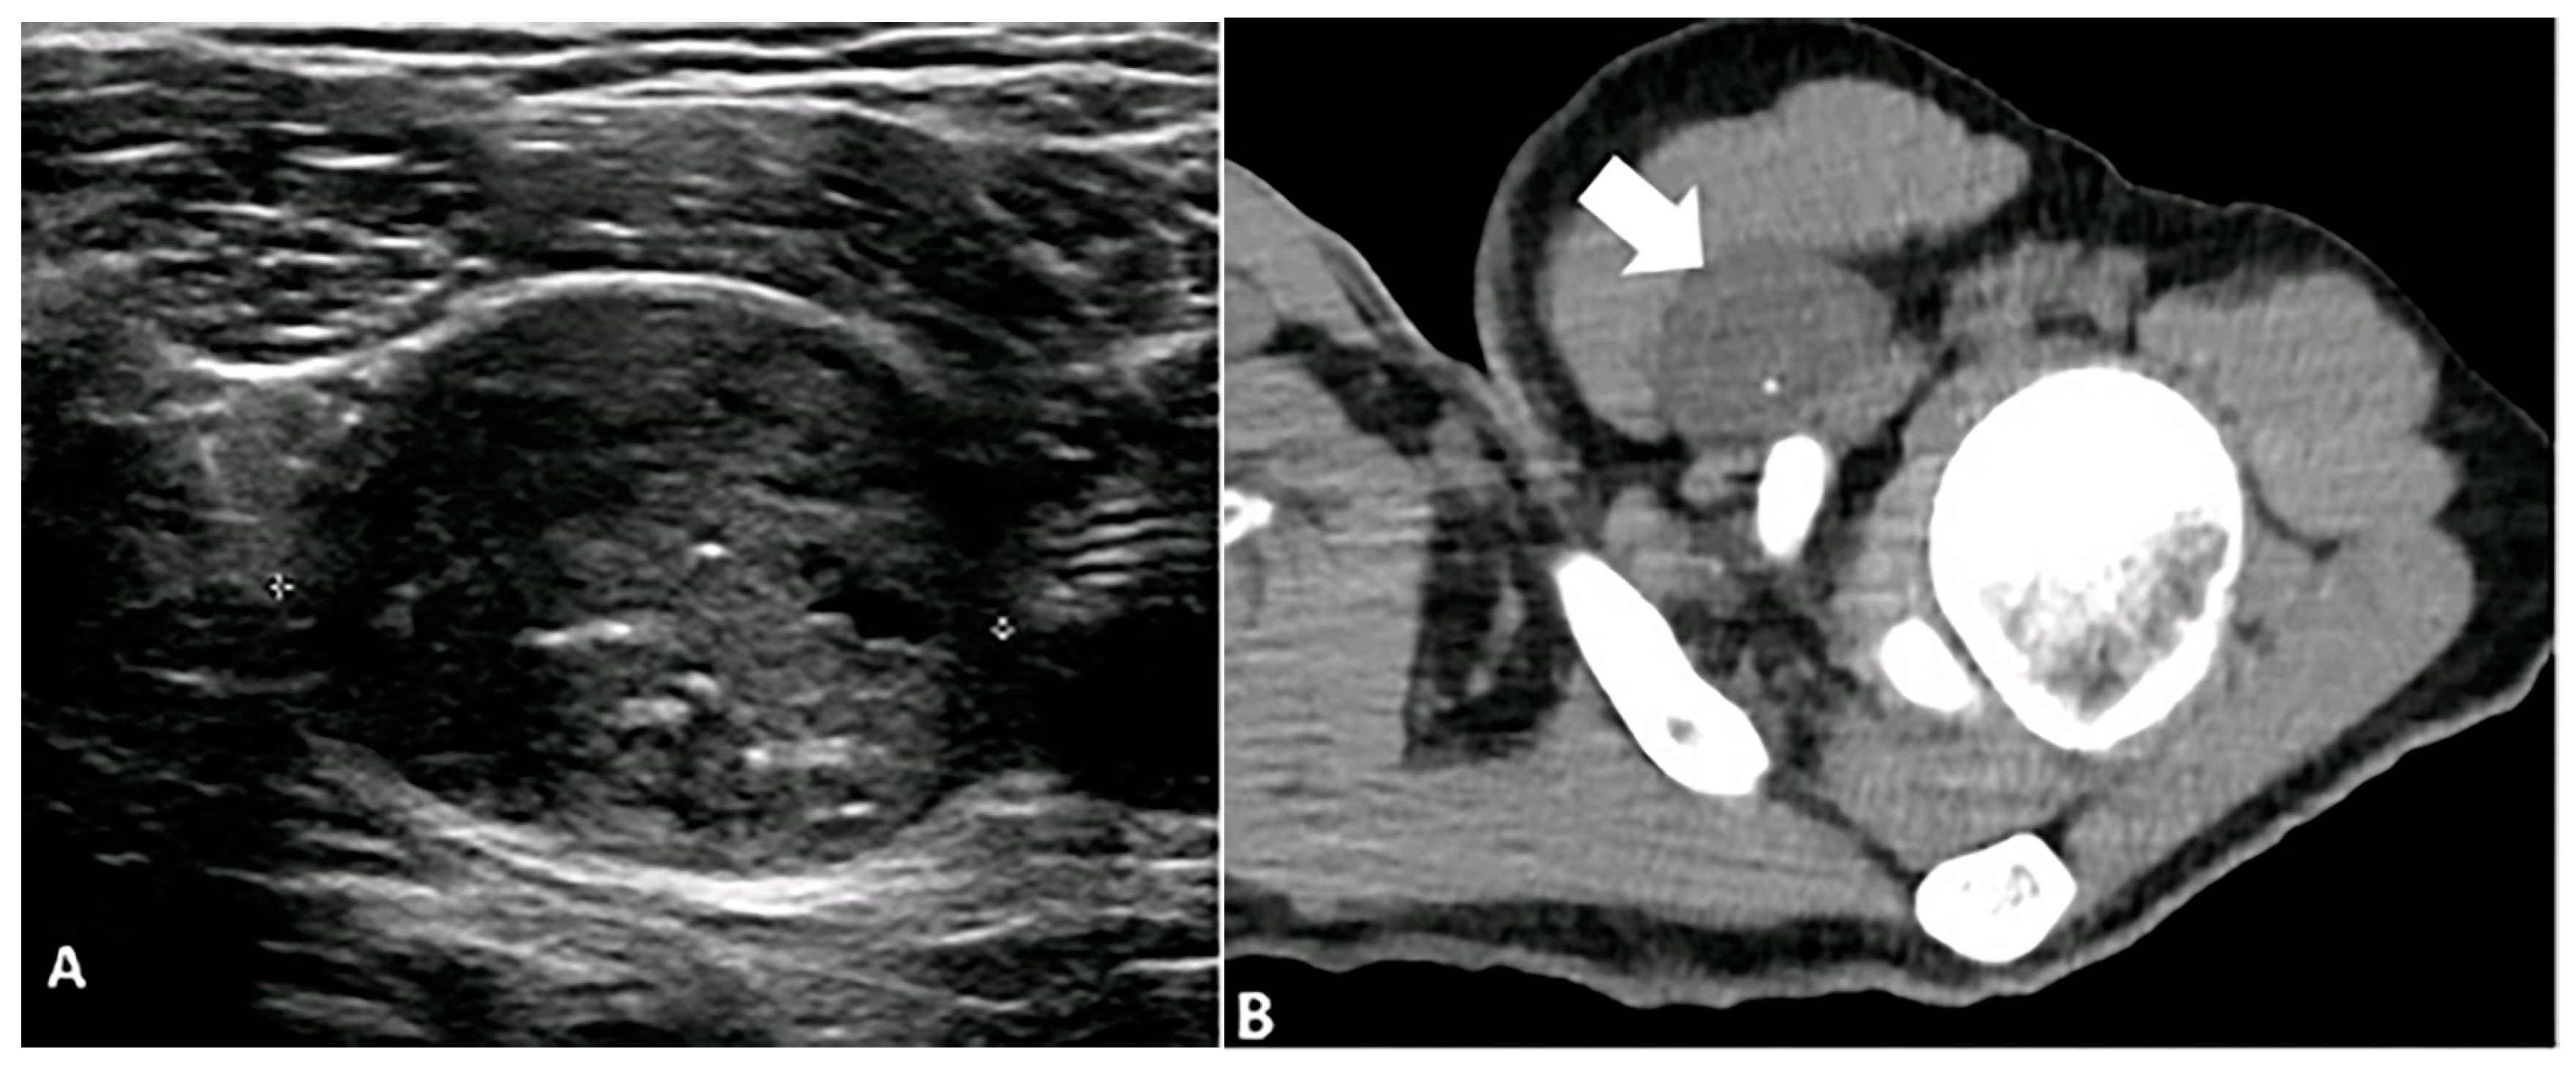

5.3. Pilomatricoma

5.4. Synovial Chondromatosis